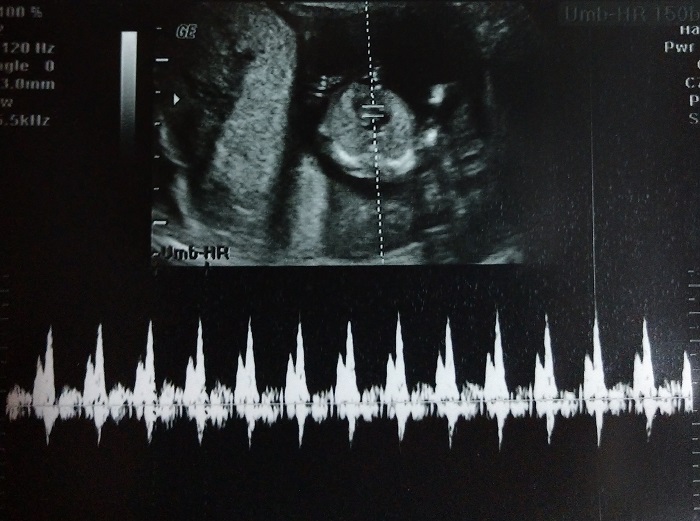

Then we were able to hear the baby’s heartbeat again. This is one of those wonderful sounds that I just love to hear.

The baby’s heart rate was 150. At the last ultrasound, the heart rate was 159-160. Our OB stated that if he had to guess, he’d say we were having a girl. Today, we’d find out if he was right.